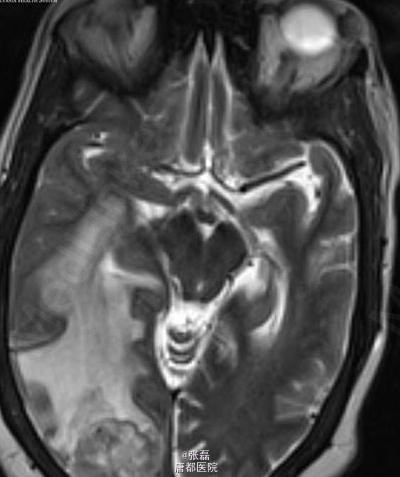

颅脑平扫 CT 显示右侧枕叶肿块,其内密度不均,中间呈低密度。周围脑组织呈血管源性水肿性低密度,邻近脑沟、裂变窄变浅,右侧侧脑室受压变形。 颅脑平扫加强化 MRI 显示:右侧枕叶见一长 T1 等长 T2 异常信号,FLAIR 呈高信号,注入对比剂后呈明显不均质强化,中间呈坏死性不强化改变。病变强化后边界不清,邻近脑实质和后方软脑膜受侵。病变定位脑内,非硬脑膜起源,未见脑膜尾征。周围脑组织可见血管源性水肿征象,累及皮层下和深部白质。MRI 显示较 CT 清晰、明显。 病理诊断:脑转移瘤